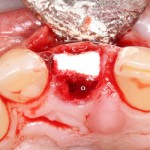

Все началось с воспаления, свищевого хода и удаления зуба:

Затем, мы готовим лунку и проверяем позиционирование импланта:

После чего аугментируем лунку. Для упаковки Bio-Oss Collagen очень удобно использовать аналоги имплантов:

Устанавливаем имплантат XiVE (Dentsply Implants):

Сразу на имплантат — временная коронка: